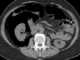

Trauma with colonic perforation

Gastrointestinal perforation, also known as ruptured bowel, is a hole in the wall of part of the gastrointestinal tract. The gastrointestinal tract includes the esophagus, stomach, small intestine, and large intestine. [Source: Wikipedia ]